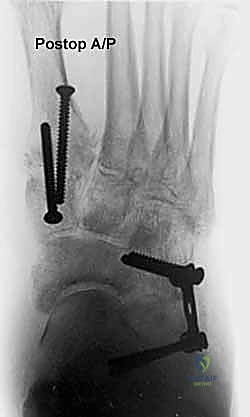

* الأشعة السينية (X-rays) مع تحمل الوزن: ضرورية لتقييم درجة انهيار القوس وزوايا العظام (مثل زاوية تالونافيكولار Meary's Angle).